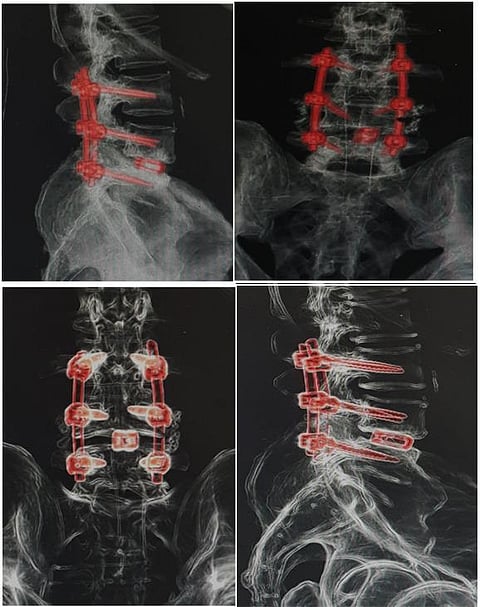

وأضاف: "أجرينا العملية الجراحية وتكللت -ولله الحمد- بالنجاح واستطاع المريض ولأول مرة منذ عامين المشي والحركة بدون ألم أو تنميل بالأطراف السفلية؛ حيث تم خلالها تثبيت الفقرات القطنية بواسطة مسامير تيتانيوم، مع تركيب قفص تيتانيوم (ألمانية الصنع)؛ بهدف رفع الضغط عن جذور الأعصاب وتوسيع القناة العصبية القطنية وتوسيع مخارج جذور الأعصاب".